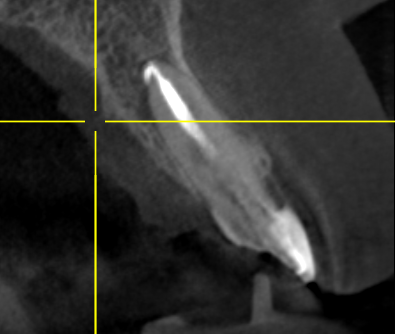

Клинический случай: пациент 21 год обратился с жалобами на боль и отек в области переднего зуба. На снимке КТ выявлено обширное воспаление (более 5мм диаметре) Проведено эндодонтическое лечение по протоколу с введением лечебной пасты на 14 дней.

киста на верхушке корня 12 зуба (очаг деструкции костной ткани)

На контрольном снимке спустя 4 месяца киста полностью зажила. Зуб спасен, пациент счастлив. Работу выполнил врач Белым Елена Сергеевна.